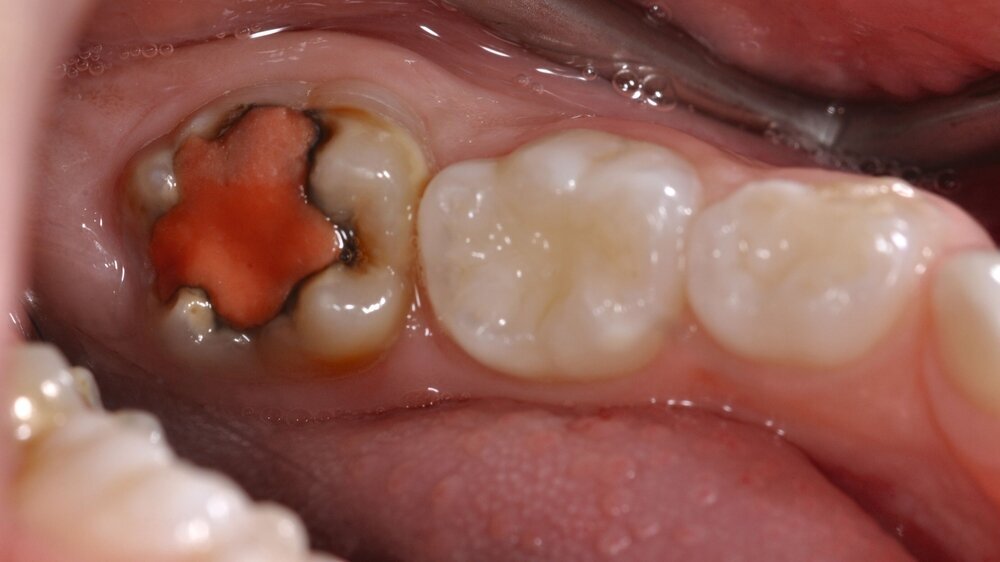

Der Vorteil der Methode ist, dass die betroffenen Zähne auch ohne Lokalanästhesie und Präparation versorgt werden können. Die temporäre Versorgung ermöglicht es, die Patienten an die zahnärztliche Behandlung zu gewöhnen. Häufig führt diese temporäre Versorgung auch zu einer Reduktion der Hypersensitivität der MIH-Zähne. Nachteil der GIZ-Versorgung ist das Risiko einer Füllungsfraktur oder eines vollständigen Verlusts der Füllung (Abbildung 4). Aktuelle Erhebungen bestätigen eine Erfolgsrate von über 80 Prozent nach einem bis zwei Jahren [Durmus et al., 2021; Mahfouz et al., 2025].

Der Behandlungsfall (Abbildung 4d) veranschaulicht die Schwächen des Verfahrens. Wird das Angebot der regelmäßigen Kontrollen nicht wahrgenommen, so droht bei Verlust der Füllung die Kariesprogression. In dem vorliegenden Fall konnte jedoch eine endodontische Maßnahme vermieden und durch die selektive Kariesentfernung die Zahnhartsubstanz weitestgehend erhalten werden.